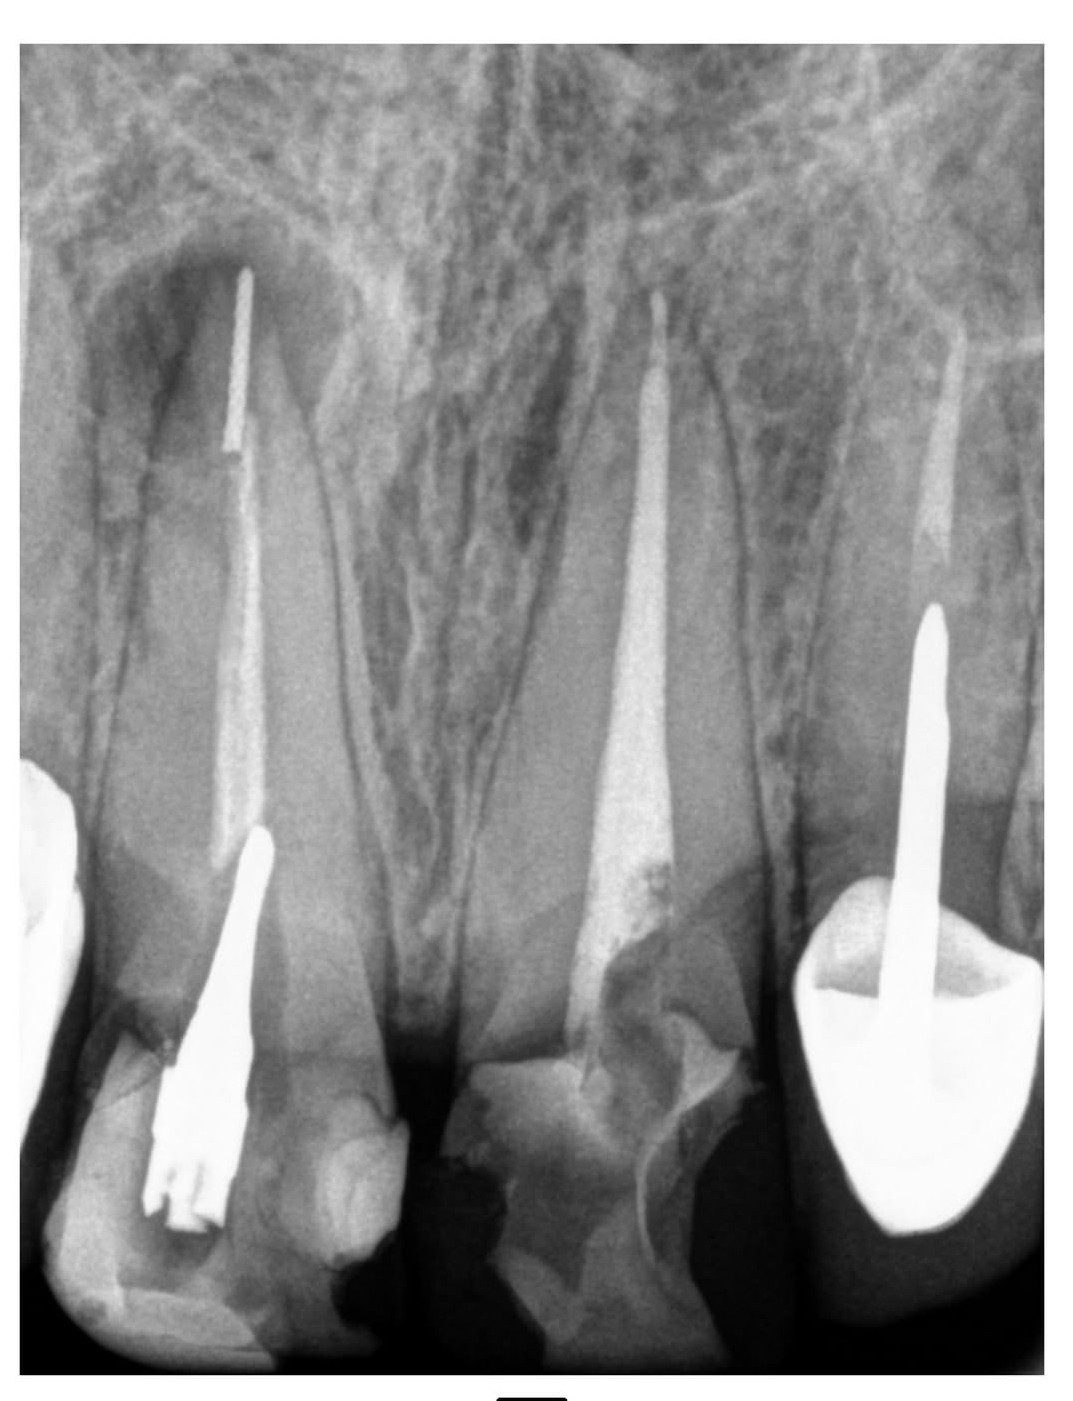

4. What option can describe the post placement in the X ray bellow for the tooth # 3.6?